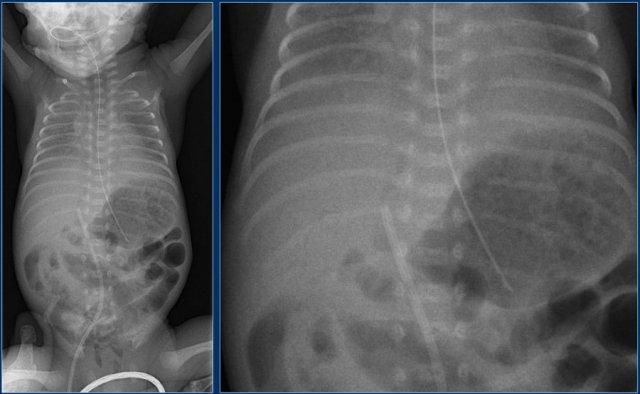

Đường truyền động mạch rốn (3)

Các phát hiện bao gồm:

- Đặt sai vị trí đường truyền động mạch rốn, bị gấp khúc trong lòng động mạch chủ bụng.